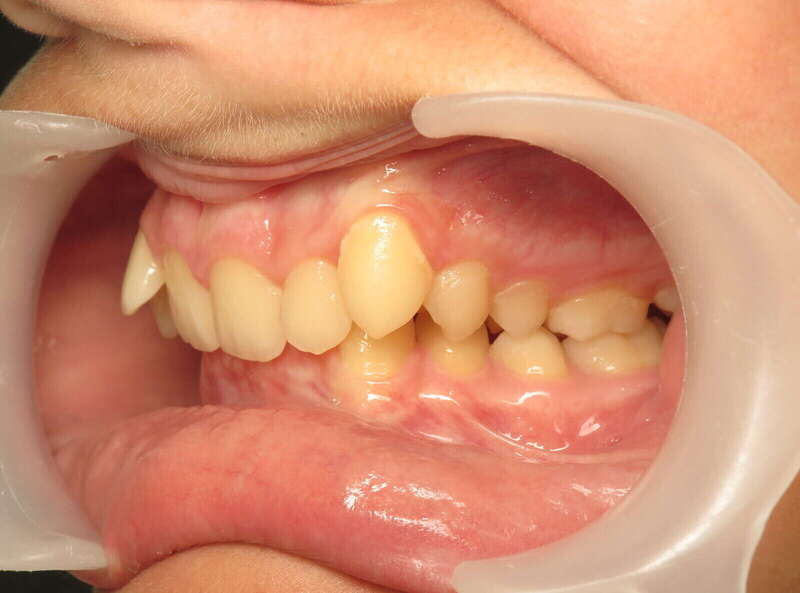

Cas n°10 traité par multi-attaches - adolescent

Ce cas d’adolescent démontre l'efficacité du traitement par brackets autoligaturants pour résoudre un encombrement majeur sans extraction. Initialement, le patient présentait des dents sévèrement chevauchées et exclues de l'arcade par manque de place.

Grâce à la technologie autoligaturante, le traitement a privilégié le développement biologique des arcades. Les forces légères et constantes ont permis d'élargir les arcades de manière physiologique, créant l'espace nécessaire pour aligner chaque dent tout en respectant l'équilibre du profil.

Résultats clés :

• Intégrité dentaire : Conservation de toutes les dents naturelles.

• Harmonie esthétique : Sourire large et aligné qui transforme l'expression faciale.

• Santé parodontale : Alignement facilitant l'hygiène et protégeant les tissus de soutien.

Ce traitement illustre parfaitement l'orthodontie moderne : une approche conservatrice qui optimise la fonction et l'esthétique sans compromis chirurgical ou extractif.